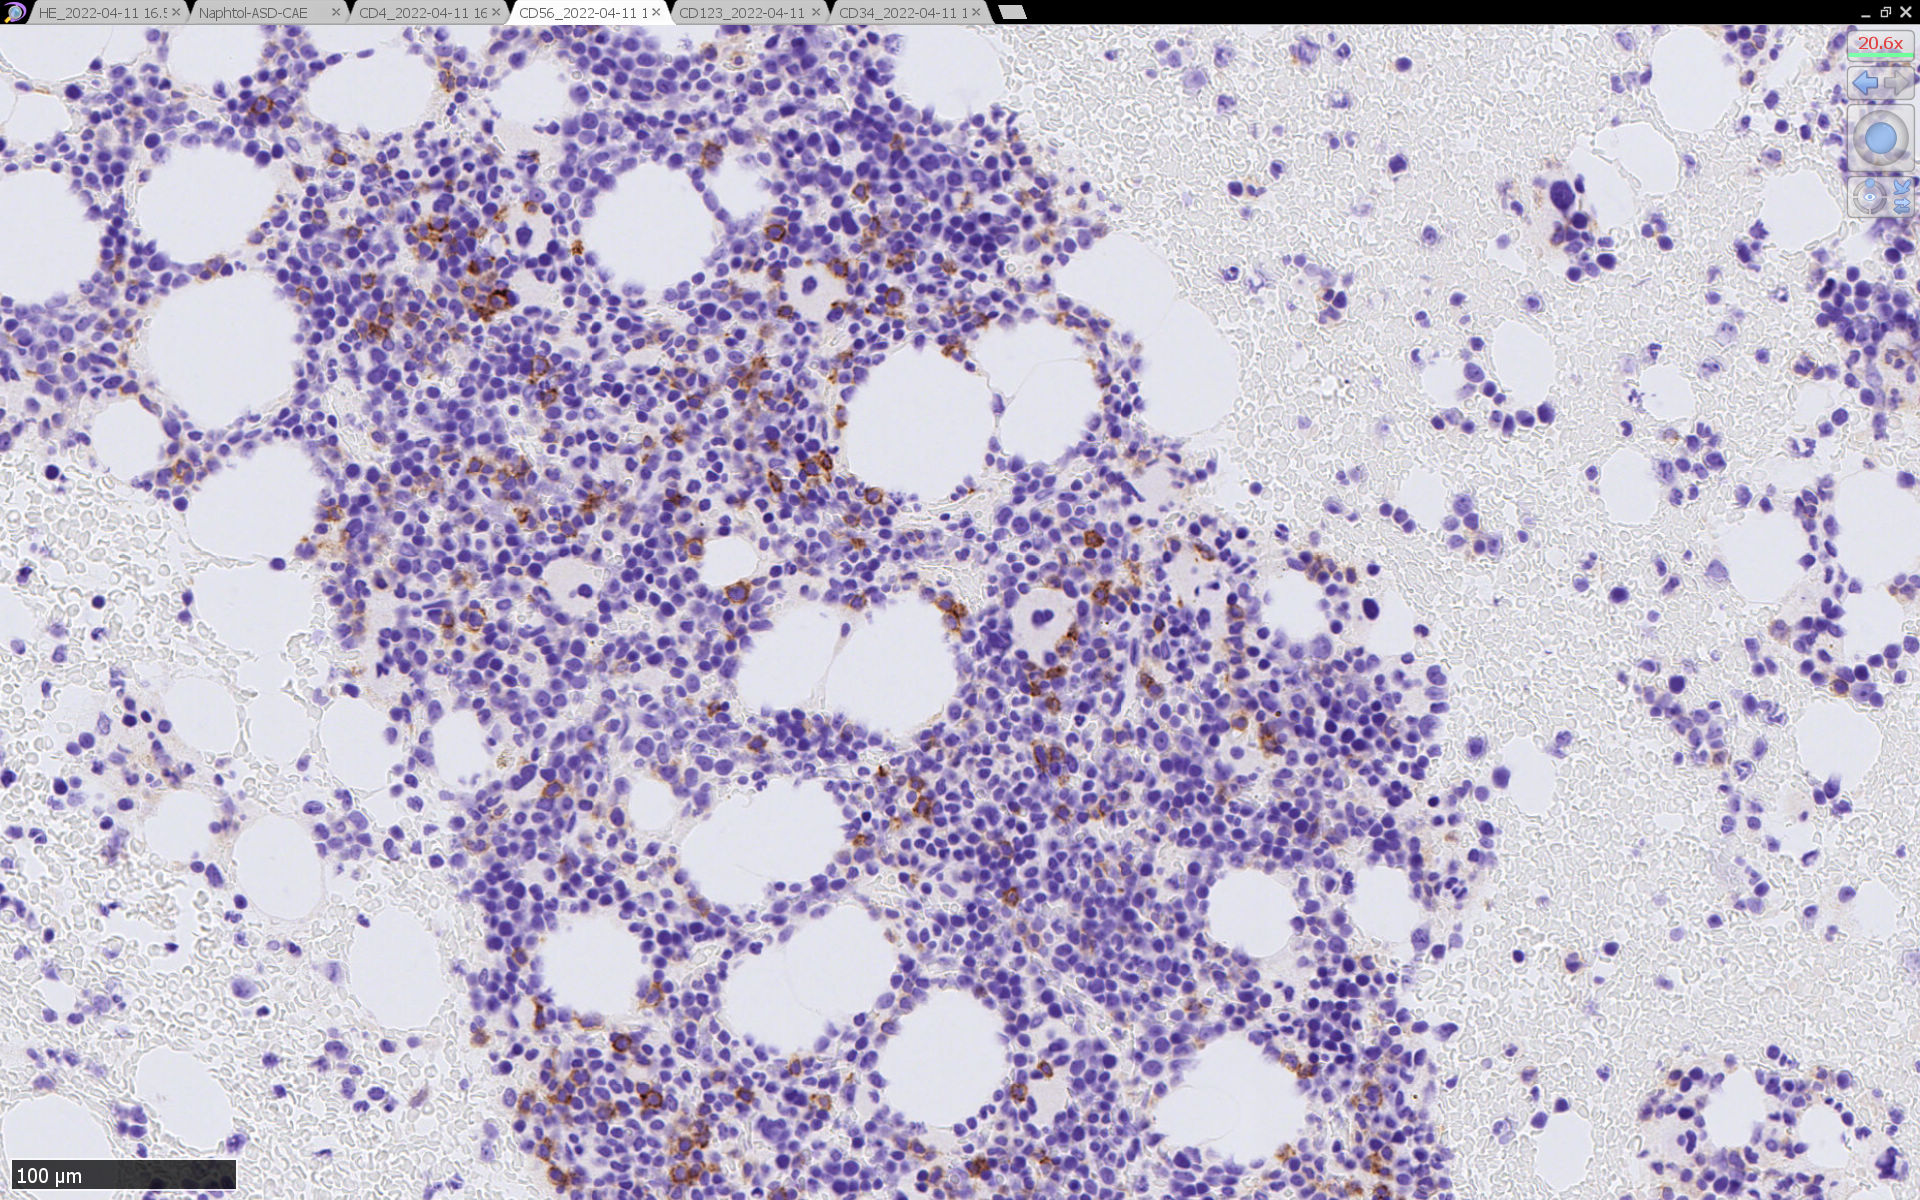

骨髄病理所見

HEでは腫瘍細胞の同定が難しい. 本症例は ASD-Giemsa染色を見ても, 腫瘍胞巣はよくわからなかった. 皮膚が先に診断がつき, 次いでBone marrowだったため, 免疫染色にすすめたが, Bone marrowが先だと診断に困ったかもしれない. 本例は, 骨髄がhypercellularで, dysplastic hematopoiesisがありMDSも疑われている.

免疫染色

CD4は染まりすぎの感がある(濃く染まる細胞はCD4+ T-cellかもしれない). CD56, CD123が陽性で可能性が高くなり, BPDCNの診断にはCD34は陰性であることが必要

TCF4、CD123、TCL1をconsultationにより染色していただき, 陽性を確認した. CD34-, lysozyme-, CD123(おいてある病院は少ないかも)をしらべて, BPDCN研究会あてconsultationをする流れでしょうか.